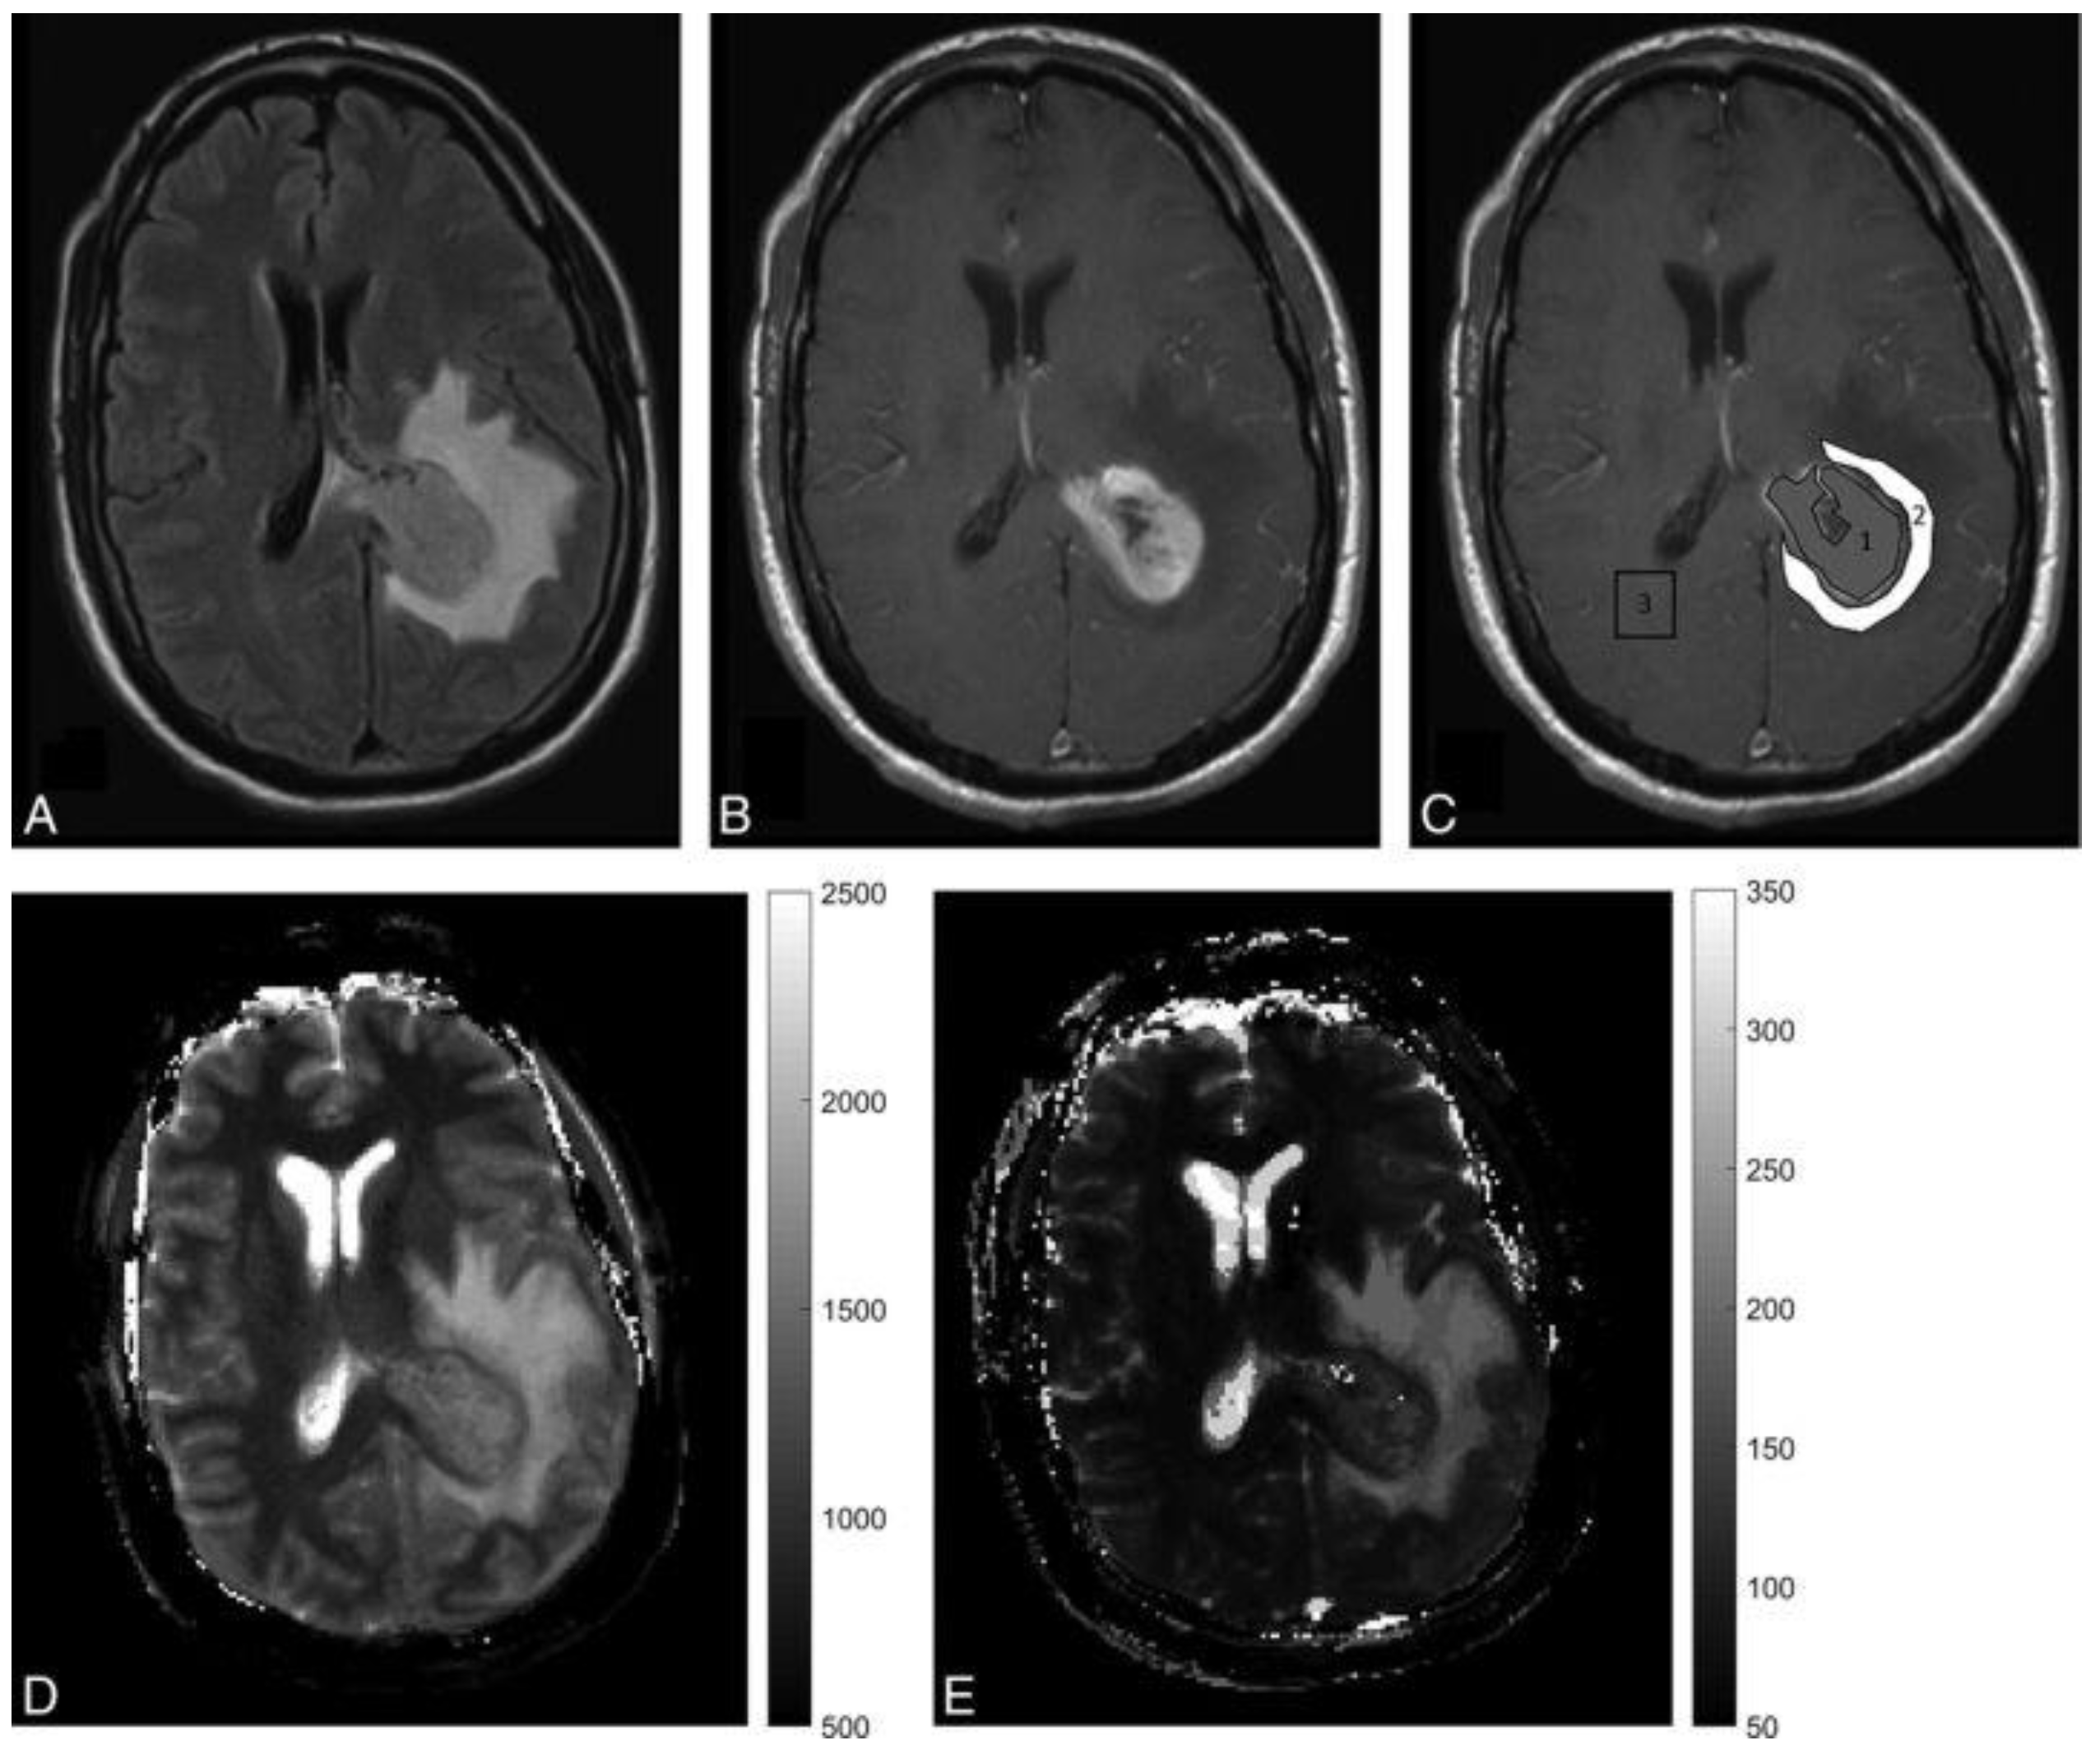

- Badve, C.; Yu, A.; Dastmalchian, S.; Rogers, M.; Ma, D.; Jiang, Y.; Margevicius, S.; Pahwa, S.; Lu, Z.; Schluchter, M.; et al. MR Fingerprinting of Adult Brain Tumors: Initial Experience. Am. J. Neuroradiol. 2017, 38, 492–499. [Google Scholar] [CrossRef] [PubMed]

- Dastmalchian, S.; Kilinc, O.; Onyewadume, L.; Tippareddy, C.; McGivney, D.; Ma, D.; Griswold, M.; Sunshine, J.; Gulani, V.; Barnholtz-Sloan, J.S.; et al. Radiomic analysis of magnetic resonance fingerprinting in adult brain tumors. Eur. J. Nucl. Med. Mol. Imaging 2021, 48, 683–693. [Google Scholar] [CrossRef] [PubMed]

- De Blank, P.; Badve, C.; Gold, D.R.; Stearns, D.; Sunshine, J.; Dastmalchian, S.; Tomei, K.; Sloan, A.E.; Barnholtz-Sloan, J.S.; Lane, A.; et al. Magnetic Resonance Fingerprinting to Characterize Childhood and Young Adult Brain Tumors. Pediatr. Neurosurg. 2019, 54, 310–318. [Google Scholar] [CrossRef] [PubMed]